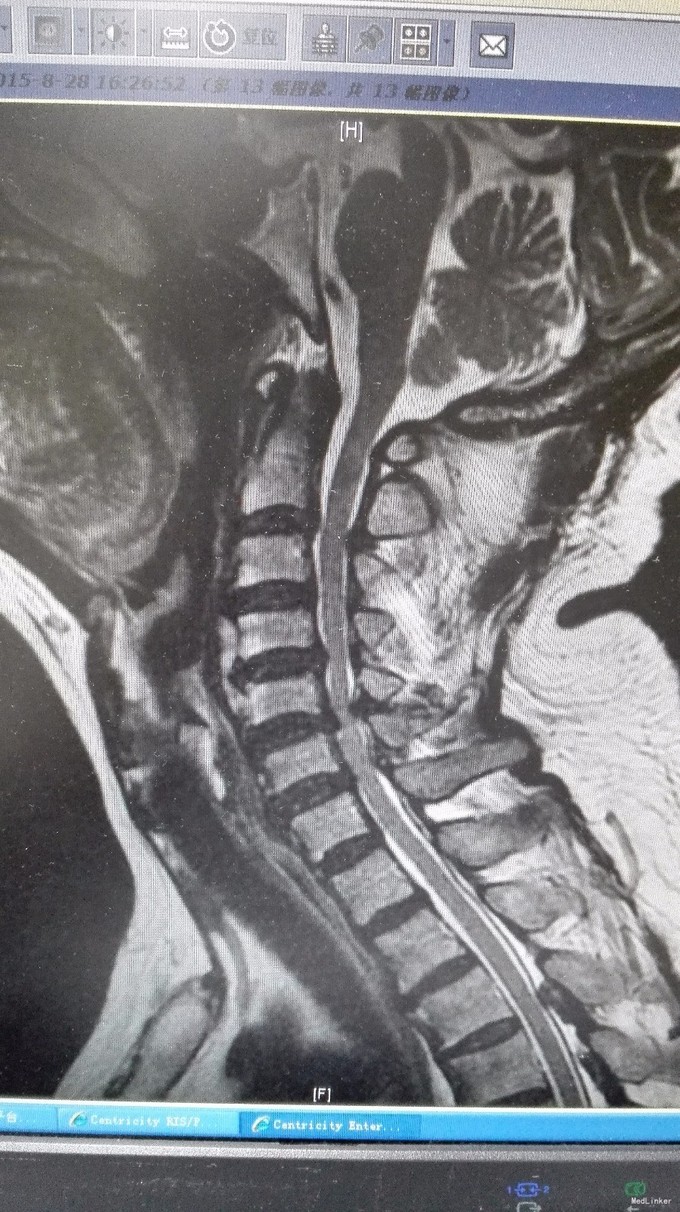

主诉:双手第2、3指尖麻木1年,加重伴双下肢沉重感4月。 病史:1年前出现双手食指、中指指尖麻木,未予以治疗,4月前出现双下肢沉重感,予以腰椎按摩后双下肢症状有所缓解,但双下肢仍有沉重感,右下肢较重,在外院诊治为颈椎病,建议手术治疗,患者拒绝,为求进一步诊治,特来我院就诊,门诊拟混合型颈椎病收入我科住院治疗。

查体:双手麻木感,肱三头肌肌腱反射活跃,左侧髂腰肌4级,臂丛牵拉实验阴性,椎间孔挤压实验阴性。 辅查:CT:C2-7椎间盘突出,继发性椎管狭窄,OPLL,OFL。

诊断:混合型颈椎病(脊髓型+神经根型) 治疗:颈后路3-7单开门椎管扩大成型术(锚定法)